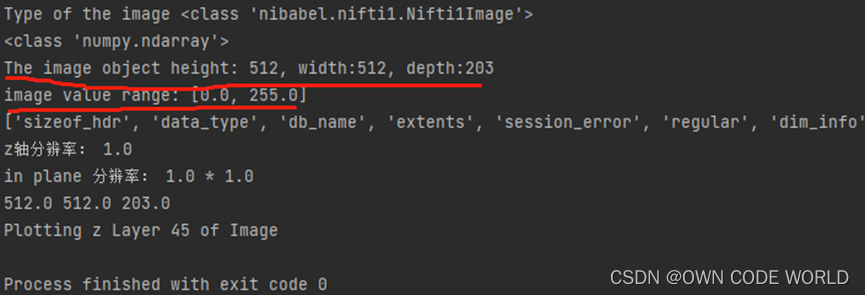

13.于是根据12的思路,去找将png转为.nii.gz的代码,先测试将一个患者的203张img和label转化为对应的img.nii.gz和label.nii.gz

转化出来的nii.gz中的维度512512203是正确的,挺高兴的,但是当我将数据集经过预处理以后,放入模型中,进行训练的时候,出现了问题。

经过查阅资料发现,是由于num_class, 即训练中分类的数量少于label数据中的标签数量导致的。通过增加num_class的值,知道256才可以进行训练,说明label数据中的标签数量为256个,分为了256类,这明显不对的,我们只有两类。但是为什么会这么多呢?返回头去看.nii.gz的信息,可以看到原始数据的label中image value range为[0,13],包含0-13,14个数据。而我们的image value range为[0,255],包含0-255,256个数据。因此推测,这14和256就是label数据中标签的数量。虽然我们用png转化的.nii.gz只有0和255两个值,但是范围仍是[0,255].